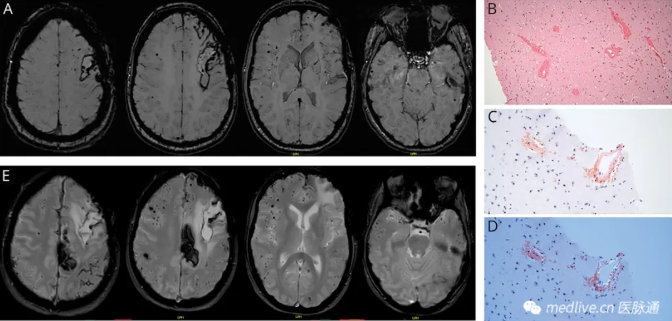

血肿清除后进行的MRI血敏感序列显示双侧脑均有多处严格意义上的脑叶微出血,提示为CAA(图2A)。血肿清除过程中进行的脑活检证实了CAA诊断,显示脑血管中存在淀粉样蛋白β沉积(图2B-D)。

图2 头颅MRI及脑活检组织学染色

(A) 血肿清除后进行的MRI磁敏感加权成像(SWI)序列显示多发脑叶微出血,提示CAA,左额叶因出血而出现含铁血黄素沉积。(B-D) 脑活检代表性皮质切片的组织化学染色;苏木精-伊红(HE)染色显示血管增厚和血管周围出血(B),×100放大;刚果红阳性血管(C)及偏振光下呈苹果绿双折射(D)显示淀粉样蛋白β沉积,×200放大;(E) 随访MRI梯度回波T2*加权成像显示疾病进展,微出血数量增加,皮质表面铁沉积及左侧额叶新发脑出血。

2023年12月的最新MRI显示疾病进展,脑微出血数量增加,双侧半球出现皮质表面铁沉积(图2E)。